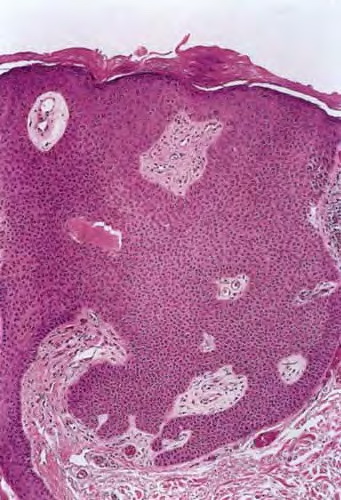

Hidroacanthoma simplex shows sharply demarcated aggregations of cuboid to ovoid cells confined to the epidermis. Eccrine poroma reveals aggregations of uniform basaloid cells that radiate from the basal layer of the epidermis into the dermis . Dermal duct tumor consists of several sharply circumscribed, mainly dermal nodules composed of poroid and cuticular cells. Ductal structures are frequently observed. Poroid hidradenoma is characterized by intradermal, solid, and cystic aggregations of poroid cells.